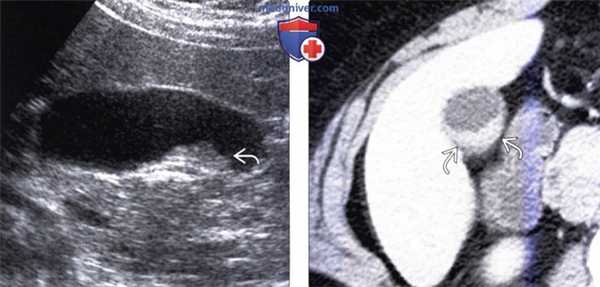

(Левый) На продольном УЗ срезе определяются два мелких холестериновых полипа . Образования неподвижны и не отбрасывают тени.

(Правый) МРТ в режиме Т2 HASTE по поводу объемного образования почки. На корональной томограмме случайно обнаружен мелкий низкоинтенсивный полип, стенка желчного пузыря не изменена.